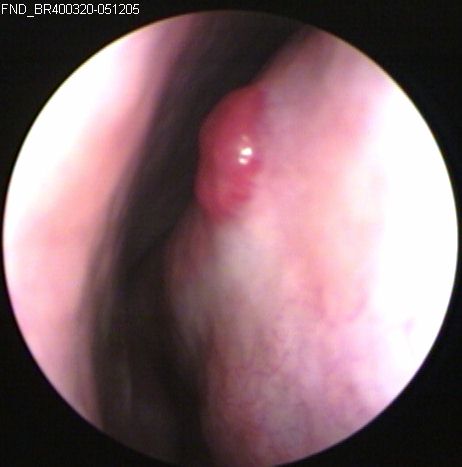

JFC. Quiste ductal de banda ventricular derecha.